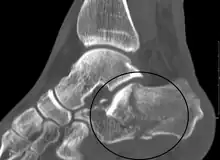

Conventional radiography is usually the initial assessment tool when a calcaneal fracture is suspected. Recommended x-ray views are (a) axial, (b) anteroposterior, (c) oblique and (d) views with dorsiflexion and internal rotation of the foot. However, conventional radiography is limited for visualization of calcaneal anatomy, especially at the subtalar joint. A CT scan is currently the imaging study of choice for evaluating calcaneal injury and has substituted conventional radiography in the classification of calcaneal fractures.[13] Axial and coronal views are obtained for proper visualization of the calcaneus, subtalar, calcaneocuboid and talonavicular joints.